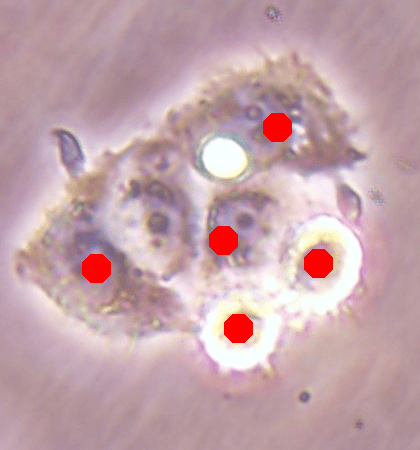

![]() |

| (a) | (b) | (c) | (d) |

Likewise, Fig. 7a shows the maps of calculated outer distances when the ground truths are given. Figs. 7b, 7c, and 7d show the outer distance maps estimated by SingleOuter, DeepDistance, and its extended version, respectively. It is observed that a single-task SingleOuter method is less accurate in estimating outer distances especially for pixels close to cell boundaries. Due to this incorrect estimation, it locates only a single cell for each of the cell pairs shown inside green ellipses, resulting in under-segmentations for these cell pairs. Our multi-task DeepDistance models yield better estimations for these boundary pixels. However, it is important to note that our models do not use the estimated outer distances in a detection algorithm but define this estimation as an auxiliary task. Particularly, this distance is defined to represent a different aspect of the problem and its estimation is considered as complementary to the main task. Concurrent learning of two related tasks with a multi-task model, which uses shared feature representations, better helps avoid local optima. In other words, when two related tasks share the same representations (with a shared encoder path), it is more difficult to finetune these representations for only one of these tasks. This is effective to obtain better learning performances for individual tasks, as also shown in Figs. 6 and 7.